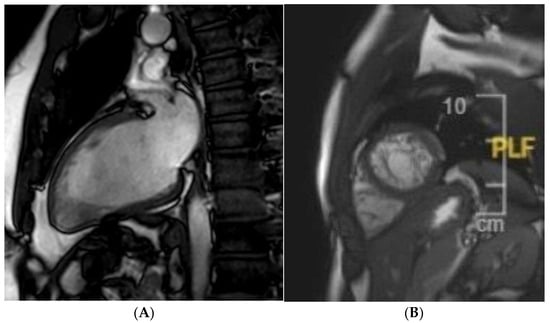

Certain subtle structural abnormalities (focal LV hypertrophy [54], mitral valve leaflet abnormalities [55], abnormal papillary muscle morphology and insertion [55], myocardial crypts [56]), which may be suggestive of early cardiomyopathy are easily missed with an echocardiography-only approach. The presence of interstitial and replacement fibrosis is also only established with cardiac MRI (Figure 2). This is especially important in athletes with an abnormal ECG who have a family history of NDLVC. The presence of a high T1 on a pre-contrast mapping sequence may be suggestive of extracellular volume (ECV) expansion and early cardiomyopathy. A high T1 should however always be interpreted in the clinical context; this finding when present in isolation is often of no clinical relevance [12]. Focal or diffuse replacement fibrosis in the absence of ventricular dilatation or dysfunction is also typical of certain genetic variants like FLNC, DSP, or Plakophillin-2 [PKP2]).

Figure 2. A mother presents to clinic for screening following the sudden death of her son who was a long-distance runner. Autopsy confirmed hypertrophic cardiomyopathy (HCM) secondary to a pathogenic TNNT2 variant. The victim’s uncle was also diagnosed with HCM in the interim and referred for transplantation. The mother was a carrier for the TNNT2 variant. The ECG was abnormal; echocardiography was normal. CMR identified mid-wall fibrosis in the lateral wall, despite the absence of left ventricular hypertrophy.